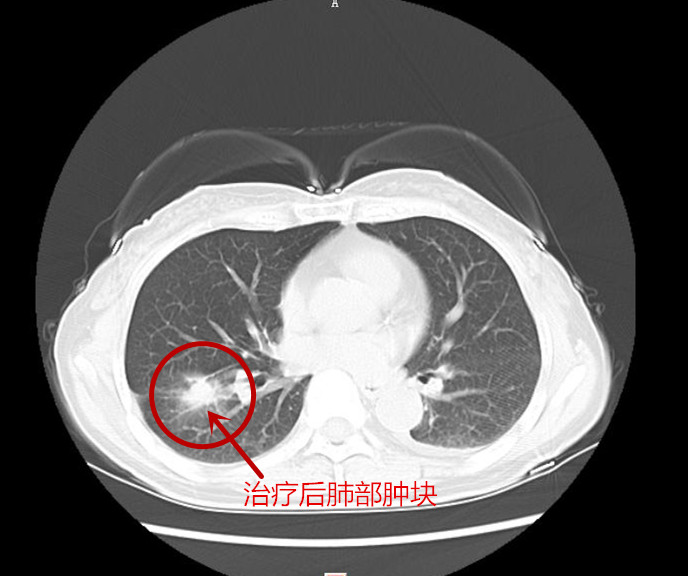

经过一段时间的治疗,张英病情稳定,医生建议可以出院在家服药治疗,但需定期复诊。6月9日患者顺利出院。在精准治疗满两个多月后,8月初,张英入院复查,经过对肺部、头部以及胸椎等处的影像学检查,结果显示肺部肿块及头部的病灶对比第一次入院时缩小了50%以上,胸9椎体的骨质破坏也得到了控制。得知结果后,她激动地对医护人员说:“感谢捷克论坛 肿瘤二科给了我第二次生命,也希望有同样遭遇的病友通过他们的宣传,能重获新生!”